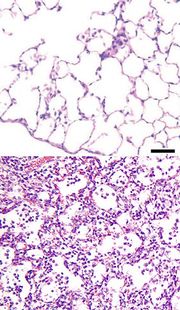

Zápal plic (pneumonie) je zánětlivé onemocnění plic. Obvykle je popisováno jako plicní parenchymální nebo alveolární zánět[1] doprovázený abnormálním plněním plic alveolární tekutinou (alveoly neboli plicní sklípky jsou mikroskopické vzduchem vyplněné váčky uvnitř plic, ve kterých probíhá výměna plynů mezi atmosférou a tělem).